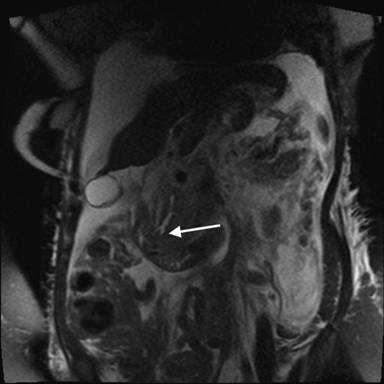

Our patient is a72-year-old woman who initially presented to an outside hospital in January 2011 with severe epigastric abdominal pain and near syncopal episode. Initial diagnostic tests revealed elevated amylase, lipase and transaminase levels. An abdominal computed tomography (CT) scan showed a diffusely edematous pancreas with peripancreatic inflammation. She was treated conservatively with bowel rest and appropriate fluid resuscitation. Once stable, she underwent magnetic retrograde cholangiopancreatography (MRCP), which indicated an intraluminal filling defect in the conjoined portion of the common bile duct and pancreatic duct near the ampulla suspicious for stone, clot or tumor (Figures 1 and 2), in addition to the marked pancreatic edema and peripancreatic inflammation (Figure 3). The patient then underwent endoscopic retrograde cholangiopancreatography (ERCP), which confirmed a lesion in the ampulla of Vater. This lesion was biopsied and thereby only partially resected. Additionally, a pancreatic stone was discovered and removed. The patient received biliary sphincterotomy and stent placement. The final pathology of the biopsy specimen revealed duodenal papillary adenoma with high-grade dysplasia. The patient convalesced from this acute episode and was discharged with planned follow-up to discuss the treatment strategy for the ampullary lesion.

Figure 1. Coronal MRCP (T2 HASTE sequence, thin slice) image demonstrating intraluminal filling defect due to ampullary lesion (white arrow). |